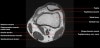

무릎 관절의 MRI 단면영상2016-08-31카테고리 106원본 보기1. Sagittal section 2. Coronal section 3. Axial section ← 이전 글전방 족근관증후군(Anterior tarsal tunnel syndrome) : 발등이 꽉 끼는 구두를 신은 후부터 발등을 누르면 아프고 엄지와 검지 발가락 사이가 저려요다음 글 →흉곽출구증후군(Thoracic outlet syndrome) : 팔이 아프고 감각이 떨어지면서 저려요같은 카테고리 글2017-06-10톰슨 검사(Thompson test) : 아킬레스건 파열을 조사하는 테스트2017-06-09Apley 압박 검사(Apley compression test) : 반월상 연골 손상을 조사하는 테스트2017-06-08맥머레이 시험(McMurray test) : 반월상 연골 손상을 조사하는 테스트← 전체 글로 돌아가기